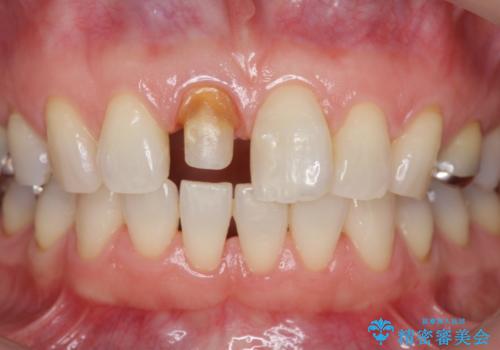

前歯の変色 セラミック審美補綴

- 前歯の変色の改善を希望され来院されました.

以前に神経が死に、根管治療を行った歯の変色が認められたためセラミックによる審美補綴治療を計画します。

神経治療を行い補綴(かぶせもの)治療を行わないと、変色が目立ち審美障害を起こすことがあります。

このような場合、セラミックによる審美改善が治療の一案として提案されます。